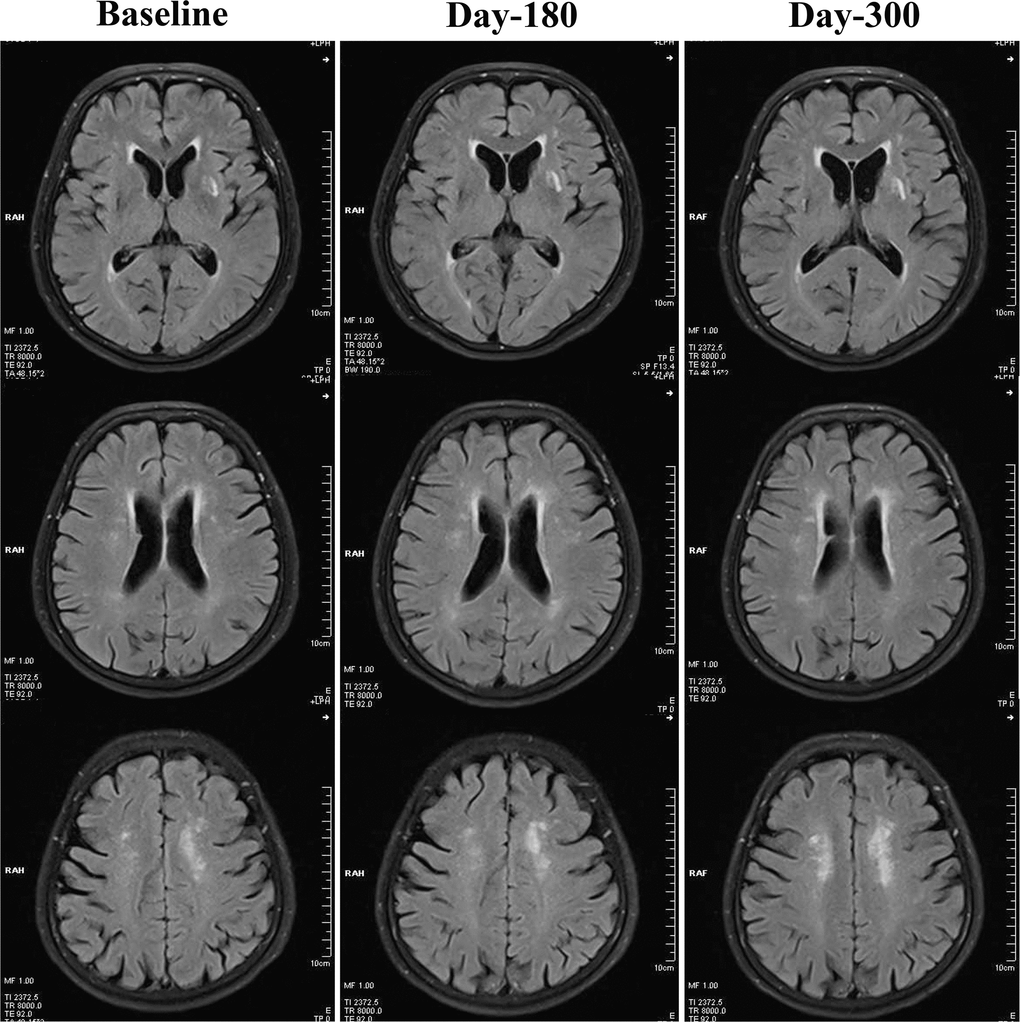

As demonstrated in Table 2, both 180-day (unadjusted p=0.001, adjusted p<0.001) and 300-day (both unadjusted and adjusted p<0.001) RIC treatments significantly decreased scores on the Scheltens scale, as compared with the control group. We also found a statistically significant reduction in the Scheltens scores of the RIC group with time and over days (180-day vs. baseline, p<0.05; 300-day vs. baseline, p<0.01), Figure 1. There was no significant difference in the Scheltens score between the baseline and the 180-day follow-up in the control group, but the score was robustly increased at 300-day (180-day vs. baseline, p>0.05; 300-day vs. baseline, p<0.001), Figure 2.

Figure 2. Changes of WMHs in the control group from baseline, day 180 to day 300. In the control group, WMHs were not significantly attenuated at day 180 or day 300, when compared with baseline levels. By contrast, WMHs seemed to be increased robustly at day 300.